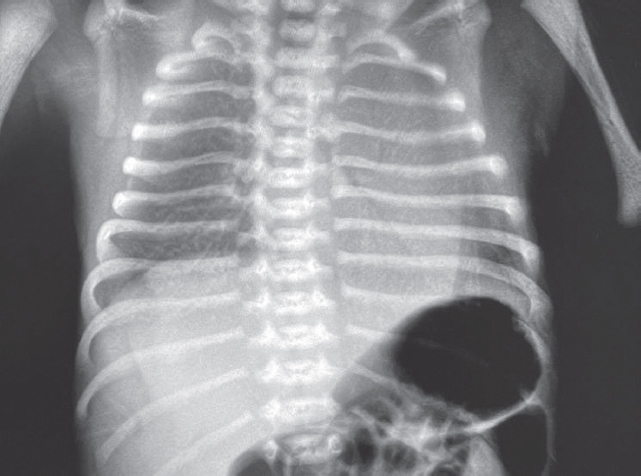

В статье представлен случай успешного лечения острого респираторного дистресс-синдрома у доношенного новорожденного, осложнившегося баротравмой легких, с применением монобронхиального введения экзогенного сурфактанта под рентгенологическим контролем. С целью оценки течения заболевания и эффективности лечения проведен ретроспективный анализ медицинской документации. С первых минут жизни у ребенка отмечались дыхательные расстройства, что стало основанием для проведения неинвазивной искусственной вентиляции легких. В динамике выявлено прогрессирование гиперкапнии и гипоксемии, в связи с чем была выполнена интубация трахеи и начата конвекциональная искусственная вентиляция легких с FiO2 = 1,0. Ключевой элемент терапии, позволивший достичь стабилизации состояния и регрессирования нарушений газообмена с полным выздоровлением пациента, — монобронхиальное введение экзогенного сурфактанта.

Монобронхиальное введение сурфактанта при остром респираторном дистресс-синдроме с гетерогенным поражением легких является эффективным вариантом лечения и может использоваться в клинической практике при рефрактерной гипоксемии.